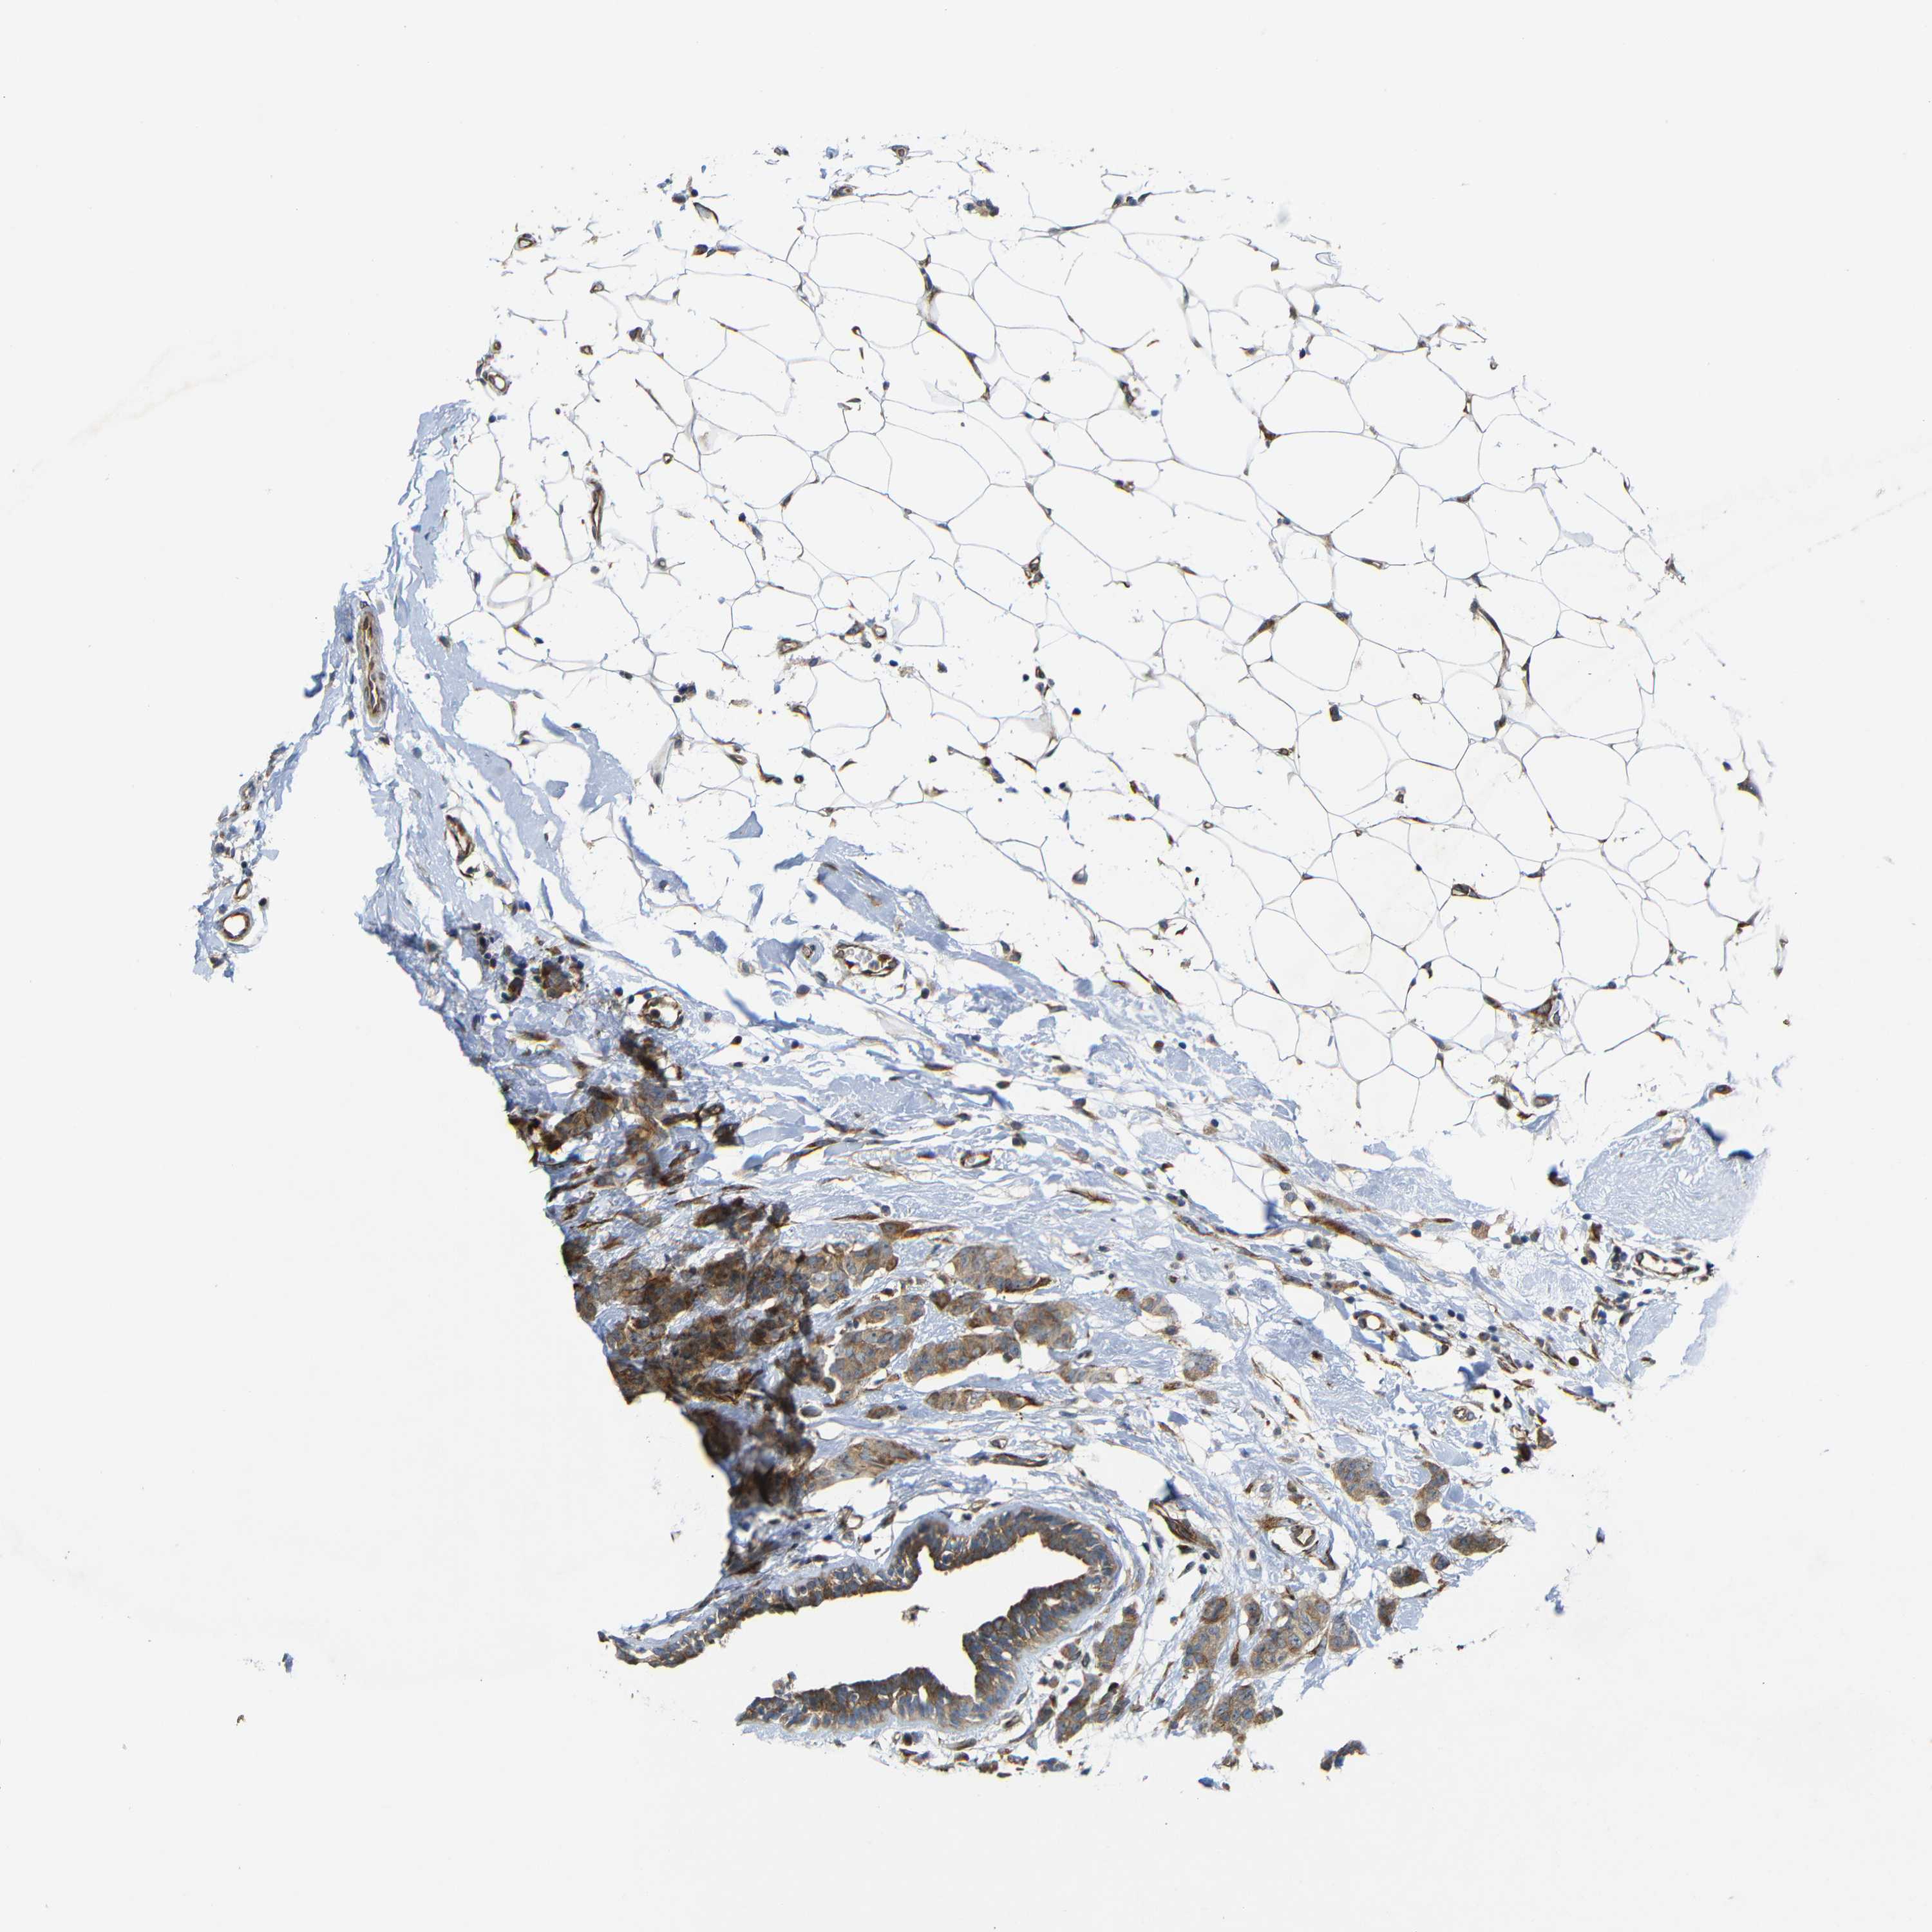

CANCER BREAST CANCER Show tissue menu

BRCA TCGA BRCA VALIDATION PROTEIN EXPRESSION